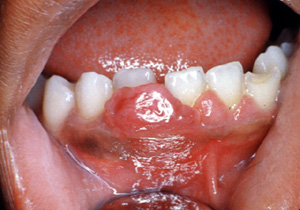

Aquí hay un ejemplo típico de un granuloma de celulas gigantes; sin embargo, sólo por la biopsia  escisional  es posible el diagnóstico.